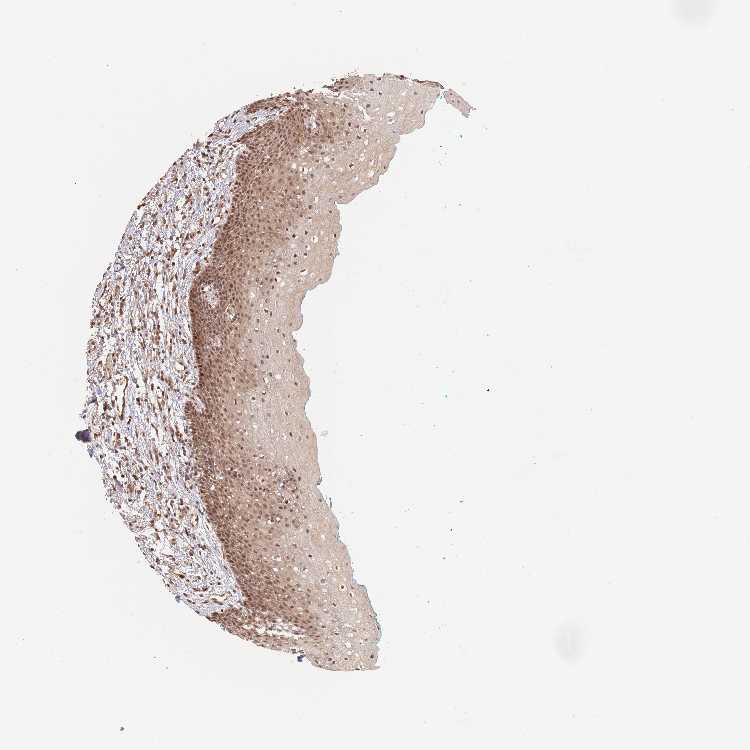

TISSUE PRIMARY DATA ORAL MUCOSA Show tissue menu

ORAL MUCOSA - Antibody stainingi

Antibody staining in the annotated cell types in the current human tissue is reported as not detected, low, medium, or high, based on conventional immunohistochemistry profiling in selected tissues. This score is based on the combination of the staining intensity and fraction of stained cells.

Each image is clickable and will lead to virtual microscopy that enables deeper exploration of all samples and also displays staining intensity scores, fraction scores and subcellular localization as well as patient and tissue information for each sample.

Antibody HPA049157

Squamous epithelial cells Medium